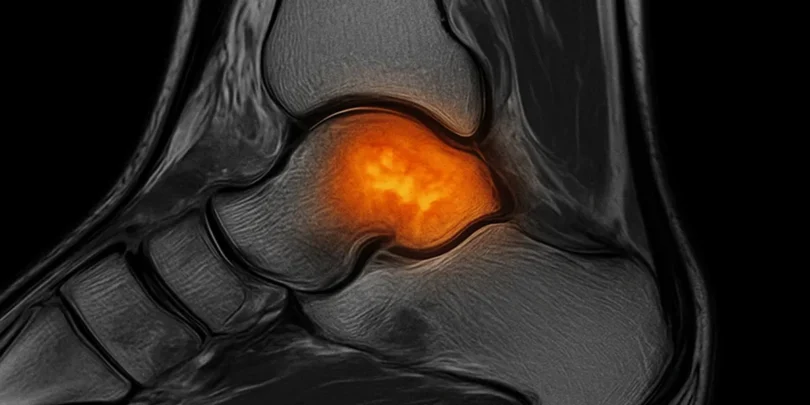

Das Knochenmarködem ist ein medizinischer Zustand, der sowohl verwirrend als auch schmerzhaft sein kann. Dabei handelt es sich um eine Ansammlung von Flüssigkeit im Knochenmark, das bei einem MRT-Bild als „Ödem“ sichtbar wird. Oft wird dieser Zustand als „Knochenprellung“ bezeichnet, was dem englischen Begriff „bone bruise“ entspricht. Diese Art von Verletzungen tritt häufig in Folge…